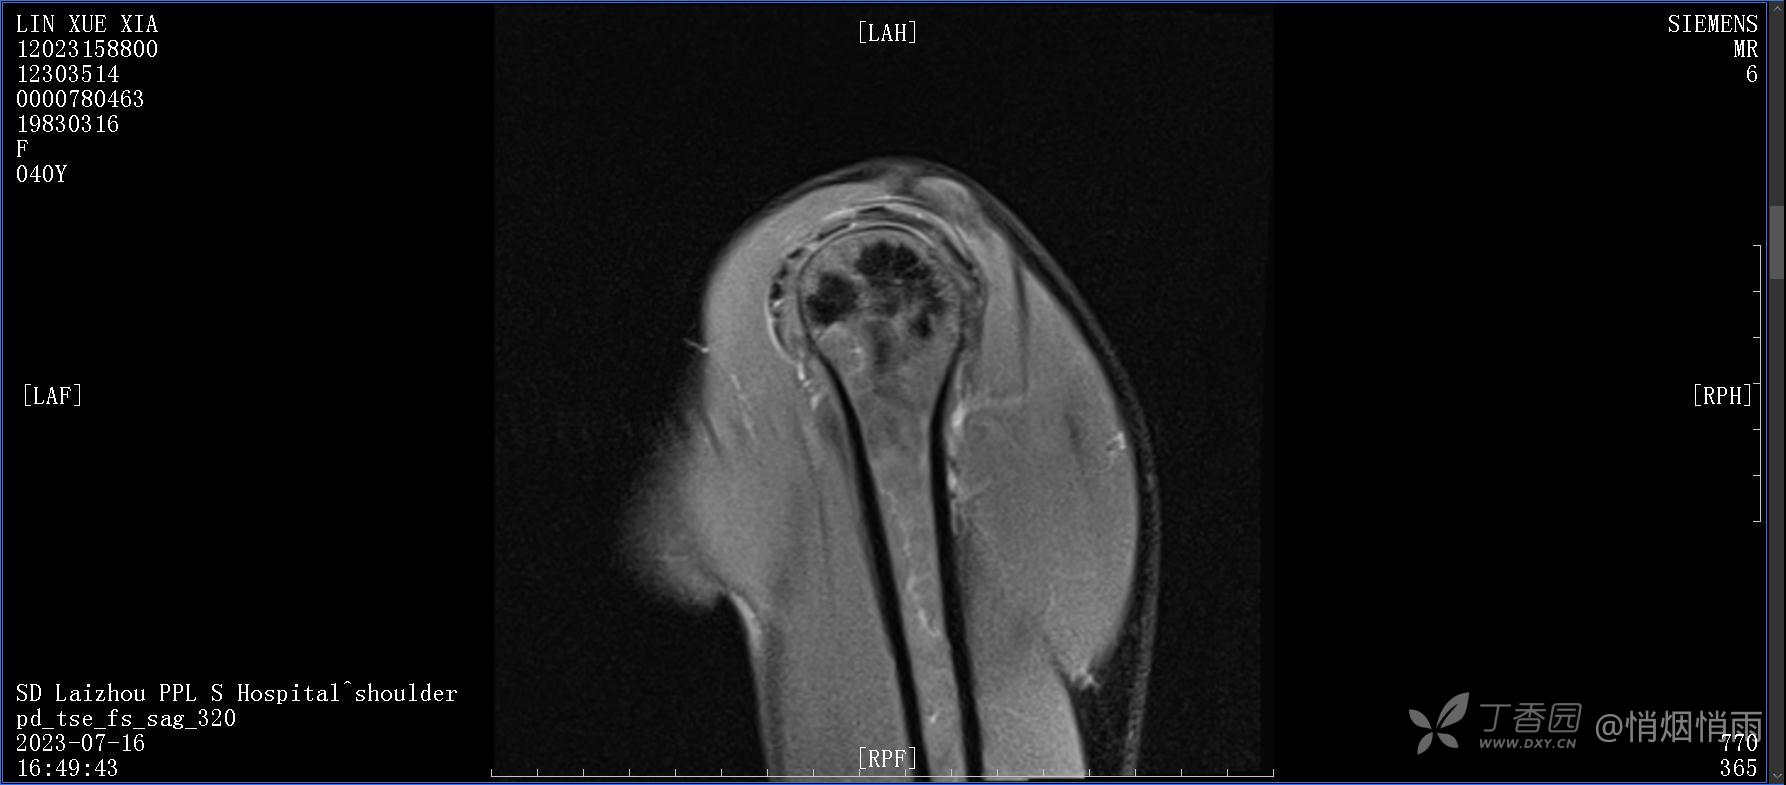

查体:右肩关节局部轻度肿胀,肩胛区压痛明显,痛处不固定,肩关节痛性活动受限,jobe test(+),lift -off test(+),中指、环指感觉较余指减退,余肢端感觉及血运情况可。

目前的诊断,暂时依据辅助检查诊为肩袖损伤,但是患者疼痛的性质和特点,却不是单纯的肩袖损伤所致。考虑过胸廓出口综合征,但是该疾病会出现肩胛区的疼痛吗?(由于考虑到费用的问题,没再进行下一步的检查)带状疱疹会有如此的症状吗?